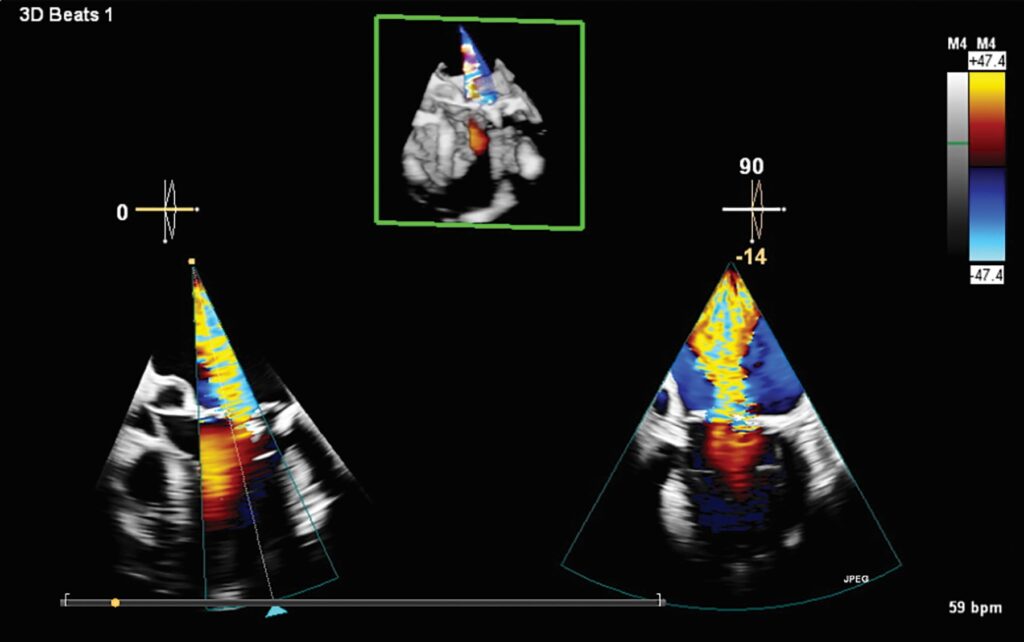

“Artificial intelligence is a tool, not a threat, and I always maintain that human plus AI is going to be better than human alone or AI alone – the 3D Auto CFQ and 3D Auto TV AI applications are examples of this, taking manual, time-consuming processes and automating these measurements in a fast, easy and reproducible way,” said Akhil Narang, MD, director, echocardiography laboratory and associate professor of medicine, division of cardiology at the Feinberg School of Medicine, Northwestern University and Bluhm Cardiovascular Institute.

Left ventricular (LV) function assessment is one of the most critical applications in cardiac imaging, playing a central role in diagnosing and managing a wide range of cardiac conditions. Transcend Plus directly supports this need by delivering fast, reproducible results that help cardiologists quickly and definitively evaluate LV function consistently across different patients and over time. Automated tools minimize operator variability, ensuring more reliable and standardized measurements, especially vital in high-volume or high-pressure clinical environments. In addition, Transcend Plus offers robust support for both contrast and non-contrast imaging. The 2D Auto EF feature enables accurate assessments even when contrast agents cannot be used, such as in patients with renal impairment. Building on this, 2D Auto EF Advanced adds AI-powered quantification capabilities for both contrast and non-contrast studies, broadening clinical applicability and enhancing measurement reliability in patients with poor image quality or challenging acoustic windows. These capabilities combine to deliver a more confident, efficient approach to cardiac care.